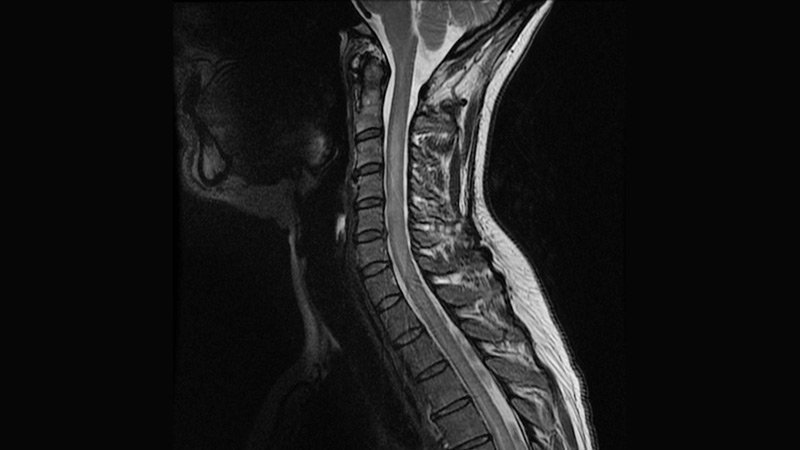

Сирингомиелия что

Сирингомиелия что 111 фотографий